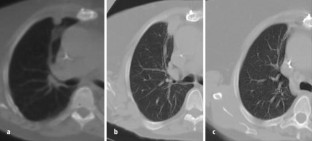

Im interdisziplinären Konsens wurden 182 Patienten (Lebertumoren: 131, andere Tumoren—Knochen, Lunge, weitere Tumoren: 51) mit 1–6 Applikatoren behandelt. Die Interventionen erfolgten in Kombination verschiedener Modalitäten (CT/MRT; CT/US) oder ausschließlich im geschlossenen MRT (1,5 T) mit direkt postinterventioneller MRT-Kontrolle.

Bei Lebertumoren wurde eine Ablationsrate von insgesamt 90,9% erzielt, die MRT erwies sich als optimale Methode zur Prozesssteuerung und direkten postinterventionellen Kontrolle. Die Komplikationsrate („major events“) betrug 5,4%. Bei nichthepatischen Tumoren ergab sich eine hohe technische Erfolgsrate mit organabhängig unterschiedlichem klinischem Erfolg.

Laser ablation was performed in 182 patients (liver tumors: 131, non hepatic tumors—bone, lung, others: 51) after interdisciplinary consensus was obtained. The procedure was done using a combination of imaging modalities (CT/MRI, CT/US) or only closed high field MRI (1.5 T). All patients received an MRI-scan immediately after laser ablation.

In 90.9% of the patients with liver tumors, a complete ablation was achieved. Major events occurred in 5.4%. The technical success rate of laser ablation in non-hepatic tumors was high, clinical results differed depending on the treated organ.

Abb. 3

Abb. 4